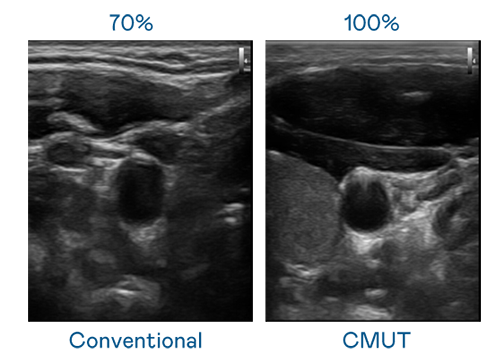

CMUT 技术是一种用电容式微机电元件来产生超音波讯号的技术。与传统 PZT 压电式技术相比,CMUT 频宽增加 30%,更宽频的超音波讯号让影像解析度大幅提升,是实现高影像品质医疗超音波扫描、促进精准医疗发展的关键技术。

大频宽带来超清晰影像

超音波影像的解析度高低,首先取决于探头能发出的讯号频宽。红桃视频传媒解说 CMUT 可提供高清晰的超音波讯号,提供高频宽、高灵敏度、影像纹理细节更高的超音波影像,协助医护人员缩短影像判读时间及利用精准的医疗影像进行诊断。